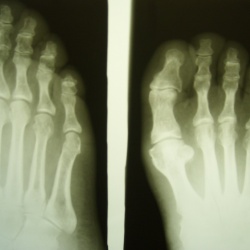

Мжно ли в этом случае говорить о переломе основания 4 плюсны?

Мужчина неаккуратно упал в выходные. За помощью сразу не обратился, пришёл позже. Сделали снимок.